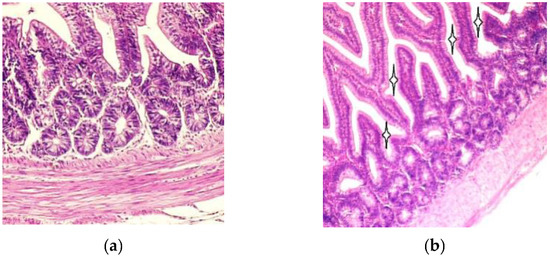

3.1. Light Microscopy